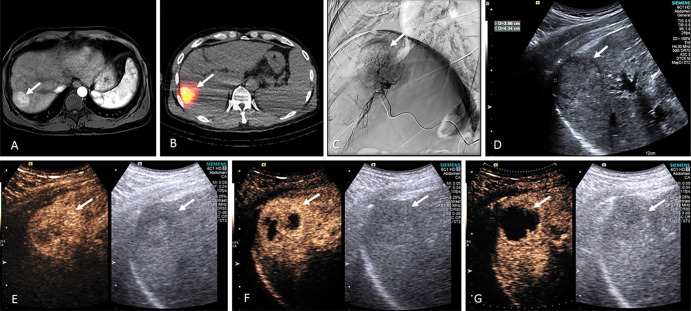

US contrast enhancement and MB destruction were observed in all examinations. Figure 3 illustrates this US-triggered MB destruction sequence in a tumor that later showed complete response 4 months after treatment. Despite treatment with local-regional embolization therapy, active blood flow still appeared within the tumor immediately following treatment because the glass microspheres (20–30 µm) do not fully occlude blood supply to the tumor (Fig 3, A). MBs were readily destroyed during US-triggered MB destruction (Fig 3, B) and reperfused back into the tumor after US-triggered MB destruction (Fig 3, C, D). Quarterly dosimetry reports from badges worn by the performing sonographer were all less than 0.08 mSv, indicating no noticeable radiation exposure during the US-triggered MB destruction examinations.

Figure 3:

Example contrast-enhanced US series show the sequence of US-triggered microbubble (MB) destruction in an 80-year-old male participant 2 hours after radioembolization. Imaging was performed in dual mode with the nonlinear contrast mode (left side of A–D) images showing MB signal and B mode (right side of A–D) used for anatomic guidance. A, Marked MB enhancement within the tumor (arrows) was observed 2 hours after radioembolization. B, At the initiation of the destructive pulse, a higher mechanical index pulse was generated, causing US-triggered MB destruction. Immediately following the 4-second destructive pulse, US-triggered MB destruction was confirmed by, C, an absence of contrast signal in the tumor and surrounding liver followed by, D, gradual MB reperfusion (required for repeat US-triggered MB destruction) back into the tumor.

Early results indicate that US-triggered MB destruction sensitizes tumors to radioembolization and may improve both tumoral response and overall participant survival. An example series from a participant deemed to have complete response at 4-month MRI follow-up is provided in Figure 4. This participant was subsequently listed for orthotopic liver transplantation. Notice the observed progression in contrast-enhanced US–derived vascularity reduction within the tumor (Fig 4, E–G).

Figure 4:

Example series of from a 54-year-old male participant undergoing hepatocellular carcinoma radioembolization with US-triggered microbubble (MB) destruction. The series shows baseline contrast-enhanced MRI scans in, A, transverse plane, B, technetium 99m macroaggregated albumin SPECT-CT in the transverse plane during treatment planning, C, angiography during yttrium 90, D, B-mode US immediately after radioembolization, and peak contrast-enhanced US enhancement during US-triggered MB destruction, E, 2 hours, F, 1 week, and, G, 2 weeks after radioembolization.